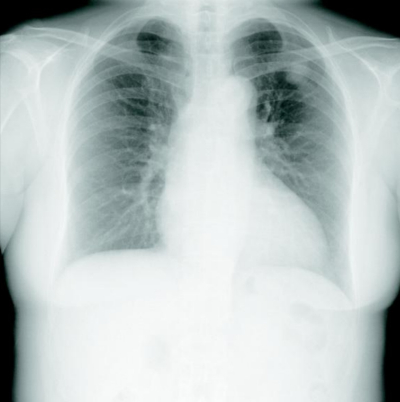

67 歳の女性。健康診断で胸部エックス線写真の異常陰影を指摘され、精査目的に来院した。喫煙歴は 25 本/日を 47 年間。

体温 36.4 ℃。脈拍 64/分、整。血圧124/76 mmHg。呼吸数 16/分。SpO₂ 97 %(room air) 。胸部 CT で異常を認めたため、気管支鏡下に擦過細胞診を施行した。胸部エックス線写真、胸部 CT及び擦過細胞診の Papanicolaou 染色標本を別に示す。

診断はどれか。